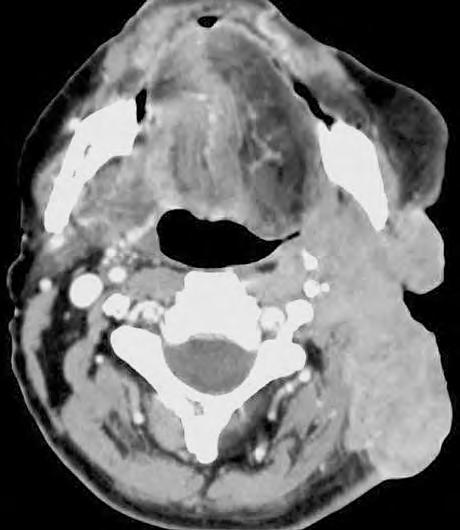

1.8.4 Germinom-nádor ze zárodečných tkání

Germinomy jsou vzácné tumory CNS (2 %), nejčastěji jsou lokalizovány vpineální krajině

Histologicky odpovídají germinálním nádorům varlat aovarií. Vmozku vyrůstají ze zadní stěny III. komory, jsou maligní. Prorůstají do hypotalamu,

Obr.

Diagnostické a léčebné postupy u maligních chorob

corpus callosum ado čtverohrbolí, metastazují všemi směry vlikvorové soustavě. Postupně utlačují mokovod azpůsobují hydrocefalus.

Léčba

Zásadní modalitou jejich léčby je radioterapie, kterou lze dosáhnout 5letého bezpříznakového přežití u90 % pacientů. Obvykle se ozařuje celý likvorový prostor celkovou dávkou 24 adalších 16 Gy se aplikuje na ložisko tumoru. Pro pacienty srecidivou se používá chemoterapie.